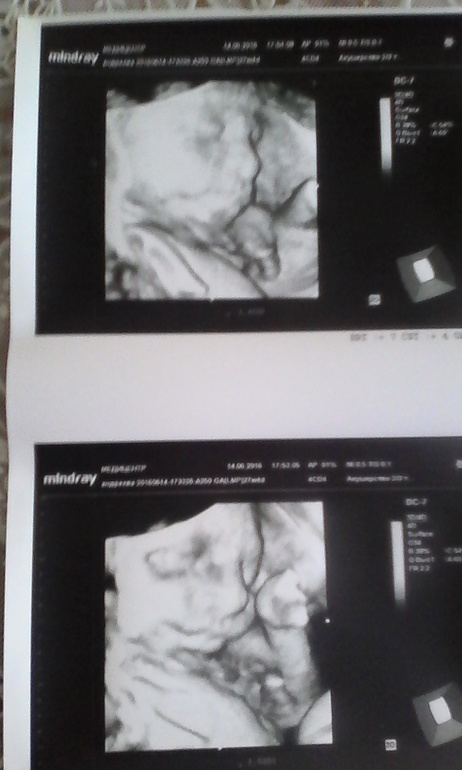

И "не вынесла душа поэта" и 14 июня мы с мужем отправились на УЗИ ( кстати в Медицентре акция- УЗИ с доплером 1800) показали нам каждый пальчик. Все у нас отлично и весим уже 1,113 гр. Единственное, это не тугое однократное обвитие вокруг шеи.